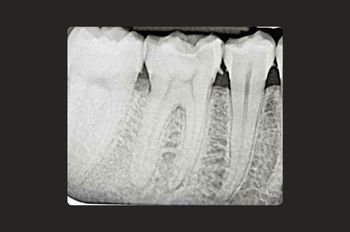

Root canal treatment is a restorative tooth-saving procedure that can avoid the need for an extraction.

Root canal treatments are a core aspect of endodontics, the dental speciality focused on treating infected tooth pulp and addressing complications from previous treatments.

Root canal treatment is needed when the tissues inside a tooth become damaged, infected, or inflamed due to deep decay, cracks, injury or repeated dental procedures on the same tooth.